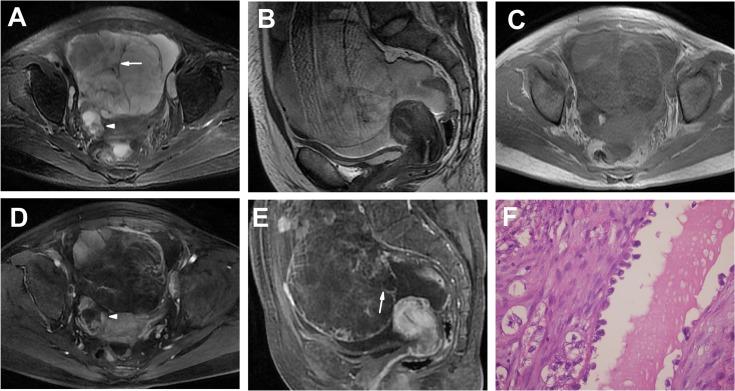

The age of the 19 patients ranged from 28 to 63 years (mean age: 53 years). Unilateral tumors were found in 17 patients (17/19, 89%); the average size of all tumors was 10.8 cm. The tumors on MRI were classified into two categories: (a) "cystic adnexal mass with solid protrusions" in 12 (57%) and (b) "solid adnexal mass with cystic areas or necrosis" in 9 (43%). For group a, high to very high SI was observed for most tumors (10/12, 83%) on T1-weighted images (T1WIs), and very high SI was observed on T2-weighted images (T2WIs) for all 12 tumors. Most solid protrusions were irregular and few in number and exhibited heterogeneous intermediate SI on T1WIs and T2WIs and prolonged enhanced SI in the contrast study. All 9 OCCCs in group b were predominantly solid masses with unequally sized necrotic or cystic areas in which some cysts were located at the periphery of the tumor (4/9, 44%). The solid components in all 9 tumors showed iso- or slightly high SI on T1WIs, heterogeneous iso-high SI on T2WIs and heterogeneous prolonged enhancement. According to FIGO classification, 14 tumors (14/19, 74%) were stages I-II, and 5 (5/19, 26%) were stages III-IV.

19例患者年龄为28至63岁(平均年龄:53岁)。17例患者(17/19,89%)为单侧肿瘤;所有肿瘤平均大小为10.8 cm。MRI上的肿瘤分为两类:(a)“伴有实性突出物的囊性附件肿块”12例(57%),(b)“伴有囊性区域或坏死的实性附件肿块”9例(43%)。对于a组,12例肿瘤中大多数(10/12,83%)在T1加权像(T1WI)上表现为高至极高SI,所有12例肿瘤在T2加权像(T2WI)上表现为极高SI。大多数实性突出物不规则且数量少,在T1WI和T2WI上表现为不均匀等SI,在增强检查中表现为强化SI延长。b组所有9例OCCC主要为实性肿块,伴有大小不等的坏死或囊性区域,其中一些囊肿位于肿瘤周边(4/9,44%)。所有9例肿瘤的实性成分在T1WI上表现为等或略高SI,在T2WI上表现为不均匀等高SI,强化不均匀且延迟。根据国际妇产科联盟(FIGO)分类,14例肿瘤(14/19,74%)为Ⅰ - Ⅱ期,5例(5/19,26%)为Ⅲ - Ⅳ期。